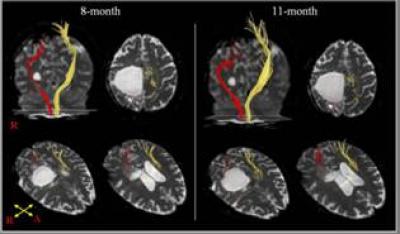

Gait dysfunction is one of the most serious disabling sequelae of stroke. Regaining gait ability in stroke is a primary goal of neurorehabilitation. Furthermore, gait is a less demanding motor function than hand function. Stroke patients can walk when motor function is recovered in the proximal joint (hip and knee), at least to the degree of being able to oppose gravity. In general, most motor recovery after stroke occurs within 3-6 months after onset, and gait function usually recovers within 3 months of stroke onset. Therefore, clinicians need to look for the cause of gait inability and perform intensive rehabilitation for stroke patients who cannot walk after 3-6 months after insult. Sung Ho Jang and team from the College of Medicine, Yeungnam University (Daegu, Republic of Korea) reported on a stroke patient who showed delayed gait recovery between 8 and 11 months after the onset of intracerebral hemorrhage, which has been reported in the Neural Regeneration Research (Vol. 8, No. 16, 2013). This 32-year-old female patient underwent craniotomy and drainage for right intracerebral hemorrhage due to rupture of an arteriovenous malformation. Brain MRI revealed a large leukomalactic lesion in the right fronto-parietal cortex. Diffusion tensor tractography at 8 months after onset revealed that the right corticospinal tract was severely injured. At this time, the patient could not stand or walk despite undergoing rehabilitation from 2 months after onset. It was believed that severe spasticity of the left leg and right ankle was largely responsible, and thus, antispastic drugs, antispastic procedures (alcohol neurolysis of the motor branch of the tibial nerve and an intramuscular alcohol wash of both tibialis posterior muscles) and physical therapy were tried to control the spasticity. These measures relieved the severe spasticity, with the result that the patient was able to stand at 3 months. In addition, the improvements in sensorimotor function, visuospatial function, and cognition also seemed to contribute to gait recovery. As a result, she gained the ability to walk independently on even floor with a left ankle foot orthosis at 11 months after onset. This case illustrates that clinicians should attempt to find the cause of gait inability and to initiate intensive rehabilitation in stroke patients who cannot walk at 3-6 months after onset.